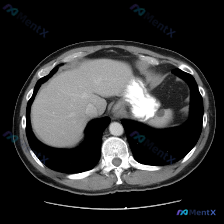

今天整理了一个很有警示意义的腹部CT病例,先看影像表现,再聊我的分析思路。 先看影像核心发现 这是一份腹部CT轴位图像: - 肝脏:实质密度均匀,血管走行正常,未见局灶性占位。 - 脾脏:形态异常,脾实质内见多发、大小不等的囊性病灶,呈圆形/类圆形,边界清晰;最大病灶位于脾中部,囊壁可见明显的环形/...

最近看到一份很有警示意义的腹部增强CT资料,整理一下思路和大家分享。 先看影像核心表现 这份是上腹部增强CT横断面软组织窗,主要异常集中在肝脏和脾脏: 1. 脾脏:体积稍大,脾实质内可见多发类圆形低密度结节灶,边界清晰,部分病灶边缘可见强化,呈「靶征」或「环形强化」改变。 2. 肝脏:肝实质内也可见...